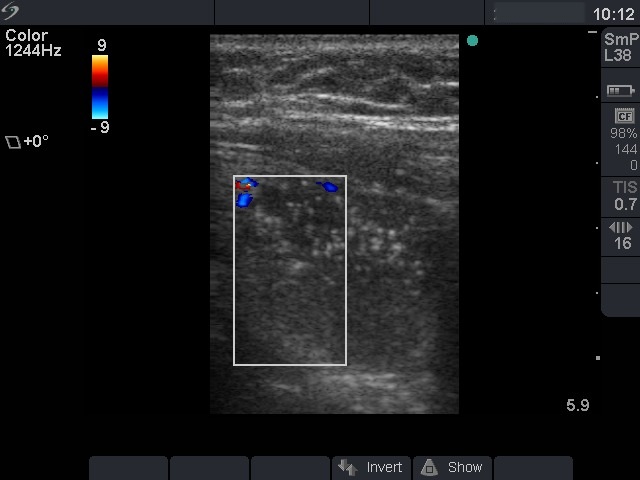

Ultrasonography: both thyroids were enlarged and echonormal. There were multiple, moderately hypoechogenic nodules in both lobes. There was a hypoechogenic nodule in the central part of the left lobe which presented hyperechogenic patches containing bright, hyperechogenic punctate granules. This pattern is similar to that observed in medullary cancer. The vascularization was not specific.